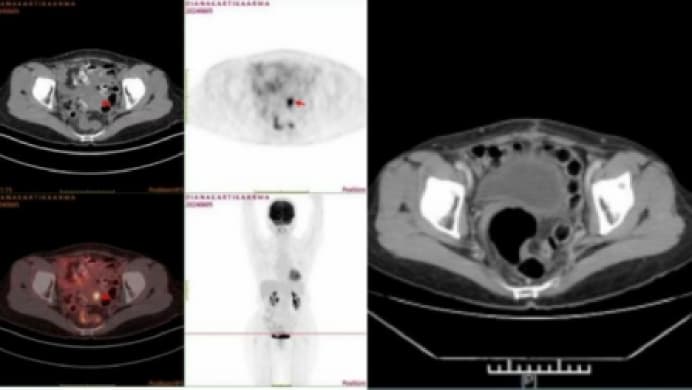

Diana Kartika Arma,

Diana Kartika Arma, kanker serviks stadium IB2B - telah bertahan 3 tahun.

Diana, seorang wanita Muslim yang berusia 57 tahun dari Jakarta, Indonesia, adalah sosok yang kuat dan tidak mudah menyerah. November 2021, ia mengalami perdarahan vagina yang tidak normal, setelah menjalani pemeriksaan, ia didiagnosis menderita kanker serviks stadium IB2, dan berat badannya turun hingga 8 kg.

Sebelum pengobatan VS setelah pengobatan

Oktober 2024, Diana datang ke Modern Cancer Hospital Guangzhou untuk mendapatkan pengobatan. Setelah menjalani rangkaian pengobatan yang disesuaikan dengan kondisinya, tumor berukuran 1.5 × 1.2 × 2.9 cm serta gejala perdarahan dinyatakan “hilang sepenuhnya”. Saat ini, kualitas hidupnya meningkat signifikan : tidur lebih nyenyak, nafsu makan membaik, dan berat badan naik kembali. Ia kini dapat menjalani hidup dengan kondisi yang jauh lebih baik.